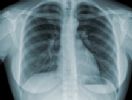

A Anvisa aprovou, nesta quinta-feira (13/11), o registro de uma nova associação de fármacos para o tratamento da tuberculose no país.

O novo medicamento traz a combinação de rifampicina+isoniazida+pirazinamida+etambutol e é indicado para tuberculose pulmonar e extra pulmonar, na fase inicial intensiva do tratamento.

O esquema básico com quatro substâncias favorece a maior adesão ao tratamento por parte do pacientes. A combinação também evita o aumento da multirresistência da doença e possibilita maior conforto ao paciente, devido à redução do número de comprimidos a serem ingeridos por dia. O registro do novo medicamento é resultante de uma parceria público privado entre os laboratórios Farmanguinhos e Lupin Limited.

A tuberculose é uma doença infecciosa e transmissível que afeta prioritariamente os pulmões, sendo uma enfermidade curável. Anualmente, são notificados cerca de seis milhões de novos casos em todo o mundo, levando mais de um milhão de pessoas a óbito. O surgimento da Aids e o aparecimento de focos de tuberculose resistente aos medicamentos agravam ainda mais esse cenário. No Brasil, a cada ano, são notificados aproximadamente 70 mil casos novos e ocorrem 4,6 mil mortes em decorrência da doença. O Brasil ocupa o 17º lugar entre os 22 países responsáveis por 80% do total de casos de tuberculose no mundo.